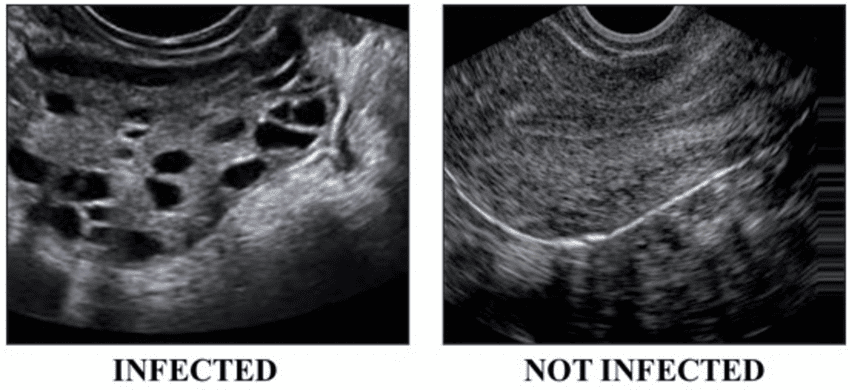

This can be evident through clinical signs (hirsutism, acne, male-pattern baldness) or confirmed via blood tests. - Polycystic Ovaries on Ultrasound

Showing 12 or more small follicles (2–9 mm in diameter) in one or both ovaries, and/or an increased ovarian volume.

This is crucial to assess for insulin resistance or the presence of pre-diabetes or Type 2 diabetes, which commonly co-exist with PCOS. - Pelvic Ultrasound

An imaging test to visually examine the ovaries. As mentioned, many cases show a characteristic “string of pearls” appearance—the hallmark of many small, underdeveloped follicles .